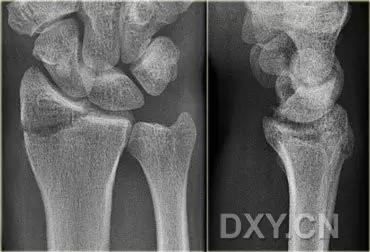

9. Essex-Lopresti 骨折

是桡骨头骨折伴有下尺桡关节脱位,导致骨间膜损伤,桡骨短缩。此种损伤,桡骨头骨折的诊断往往是明确的,容易忽视的是下尺桡关节脱位,特别是早期,下尺桡关节的症状不明显,X 线表示也不明显。

Essex-Lopresti 损伤。前后位(A)和侧位(B)示桡骨头关节内骨折(白色实线箭头);(C~E)伤后 1 个月复诊,患者诉腕关节疼痛,X 线(C,D)发现下尺桡关节脱位,(E)CT 进一步证实损伤的存在 (来源:Radiol Clin North Am. 2015 Jul;53(4):717-36)